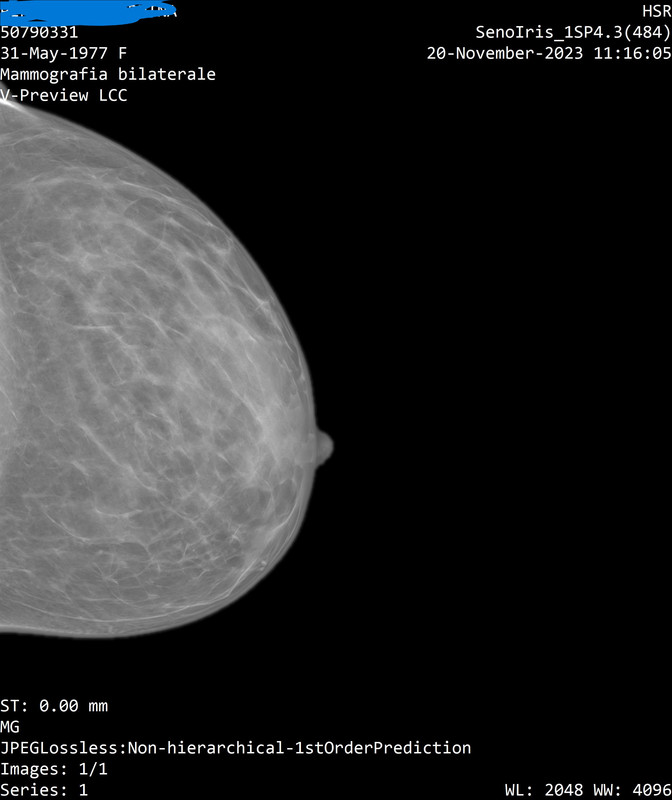

Onestamente non capisco neppure quale sia la mammella destra dalla sinistra...

Il referto dice:

"a dx al passaggio tra i quadranti inferiori e' meglio visibile un focolaio di microcalcificazioni, non riconoscibile con certezza all'ecografia mirata, meritevole di caratterizzazione mediante agobiopsia con sistema VAB sotto guida mammografica